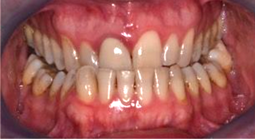

Fig 8. A class III adult male patient required surgical orthodontic treatment. The patient had anterior and posterior crossbites and required leveling of a deep curve of Spee during presurgical orthodontics.

Figure 8

Fig 9. A class III adult male patient required surgical orthodontic treatment. The patient had anterior and posterior crossbites and required leveling of a deep curve of Spee during presurgical orthodontics.

Figure 9

Fig 10. A class III adult male patient required surgical orthodontic treatment. The patient had anterior and posterior crossbites and required leveling of a deep curve of Spee during presurgical orthodontics.

Figure 10